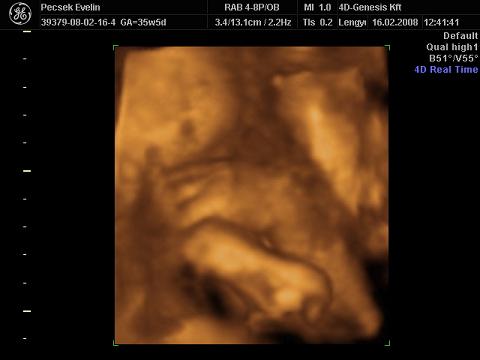

kezével csikizi a saját kis talpát :lol: :

Kép